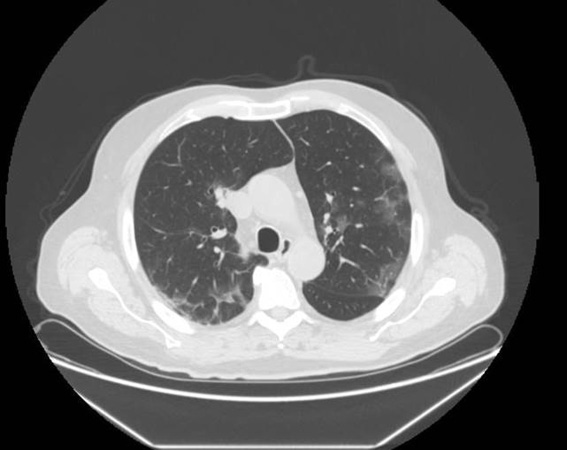

Figure 1. Chest CT: early features of COVID-19 pneumonia. Multiple patchy pure ground glass opacities (GGOs) may be seen.

COVID-19 pneumonia is common. The early chest CT features are multiple patchy pure ground glass opacities (GGOs) or GGOs with consolidation in the peripheral zone of the lung, often with vascular thickening and the crazy paving pattern, air bronchogram sign, or halo sign (Figure 1) [19].